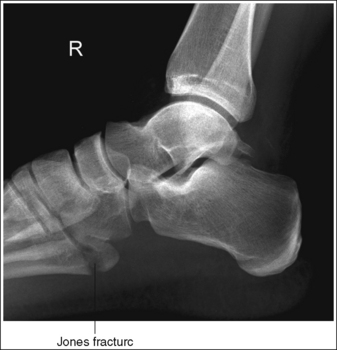

The tibiotalar joint is at the center of the exposure field. The talus, 1 inch (2.5 cm) of the fifth metatarsal base, the surrounding ankle soft tissue, and the distal fourth of the fibula and tibia are included within the collimated field.

• Centering a perpendicular central ray to the ankle midline at the level of the palpable medial malleolus places the tibiotalar joint in the center of the collimated field (Figure 6-62).

• Open the longitudinal collimation enough to include the calcaneus and one fourth of the distal tibia and fibula. Transversely collimate to include 3 inches (7.5 cm) of the proximal forefoot, ensuring that approximately 1 inch (2.5 cm) of the fifth metatarsal base is included on the image. An inversion injury of the foot and ankle may result in a fracture of the fifth metatarsal base, known as a Jones fracture (Figure 6-63). Including the fifth metatarsal base on the lateral ankle projection allows it to be evaluated for a Jones fracture.

• Either half of a 10- × 12-inch (24- × 30-cm) detailed screen-film IR placed crosswise or a single 8- × 10-inch (18- × 24-cm) computed radiography IR placed lengthwise should be adequate to include all the required anatomic structures.